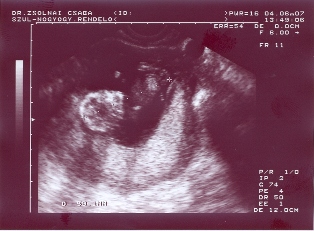

Sziasztrok!

Ezek az én drágám a kis ficergék!minden ok velük és velem is!Zárt méhszáj,mehetek tornázni és úszni is!

59mm-es mindkettő baba!Nyakiredő is ok volt!Genetikaira nem kell mennem!Hurrá!!!!!!